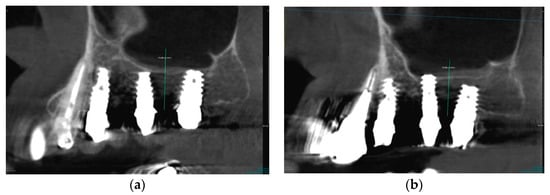

1. Introduction

2.6. Case Study